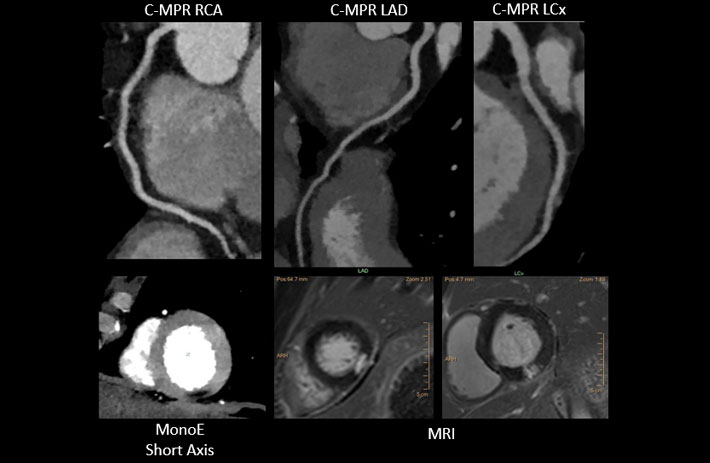

Mit dem Spektral-Detektor-CT werden Spektraldaten automatisch bei jedem Scan erfasst. Die Informationen stehen jederzeit auf der Scankonsole, der CT-Workstation sowie an jedem PACS-Arbeitsplatz zur Verfügung, sodass es nicht notwendig ist, den Patienten erneut zu scannen, bspw. wenn initial zufällige Anomalien festgestellt wurden. Dadurch profitieren Anwender durch eine höhere Diagnosesicherheit und weniger Nachuntersuchungen auf anderen bildgebenden Systemen. Unsere Fallsammlung zeigt, welchen klinischen Mehrwert der Spektral-Detektor-CT in unterschiedlichsten Anwendungsbereichen in der klinischen Routine bringt. Jede Woche gehen neue Fälle live.